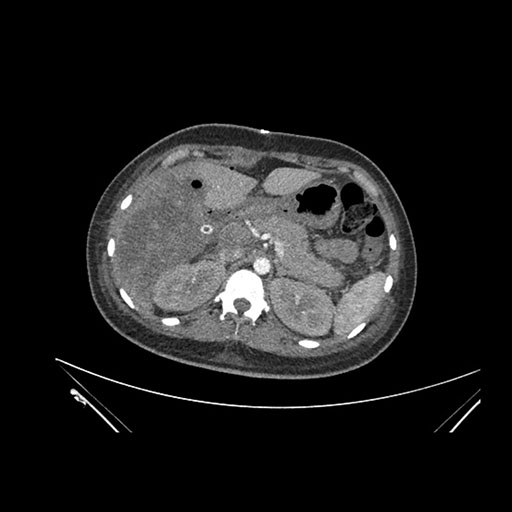

Axial Venous